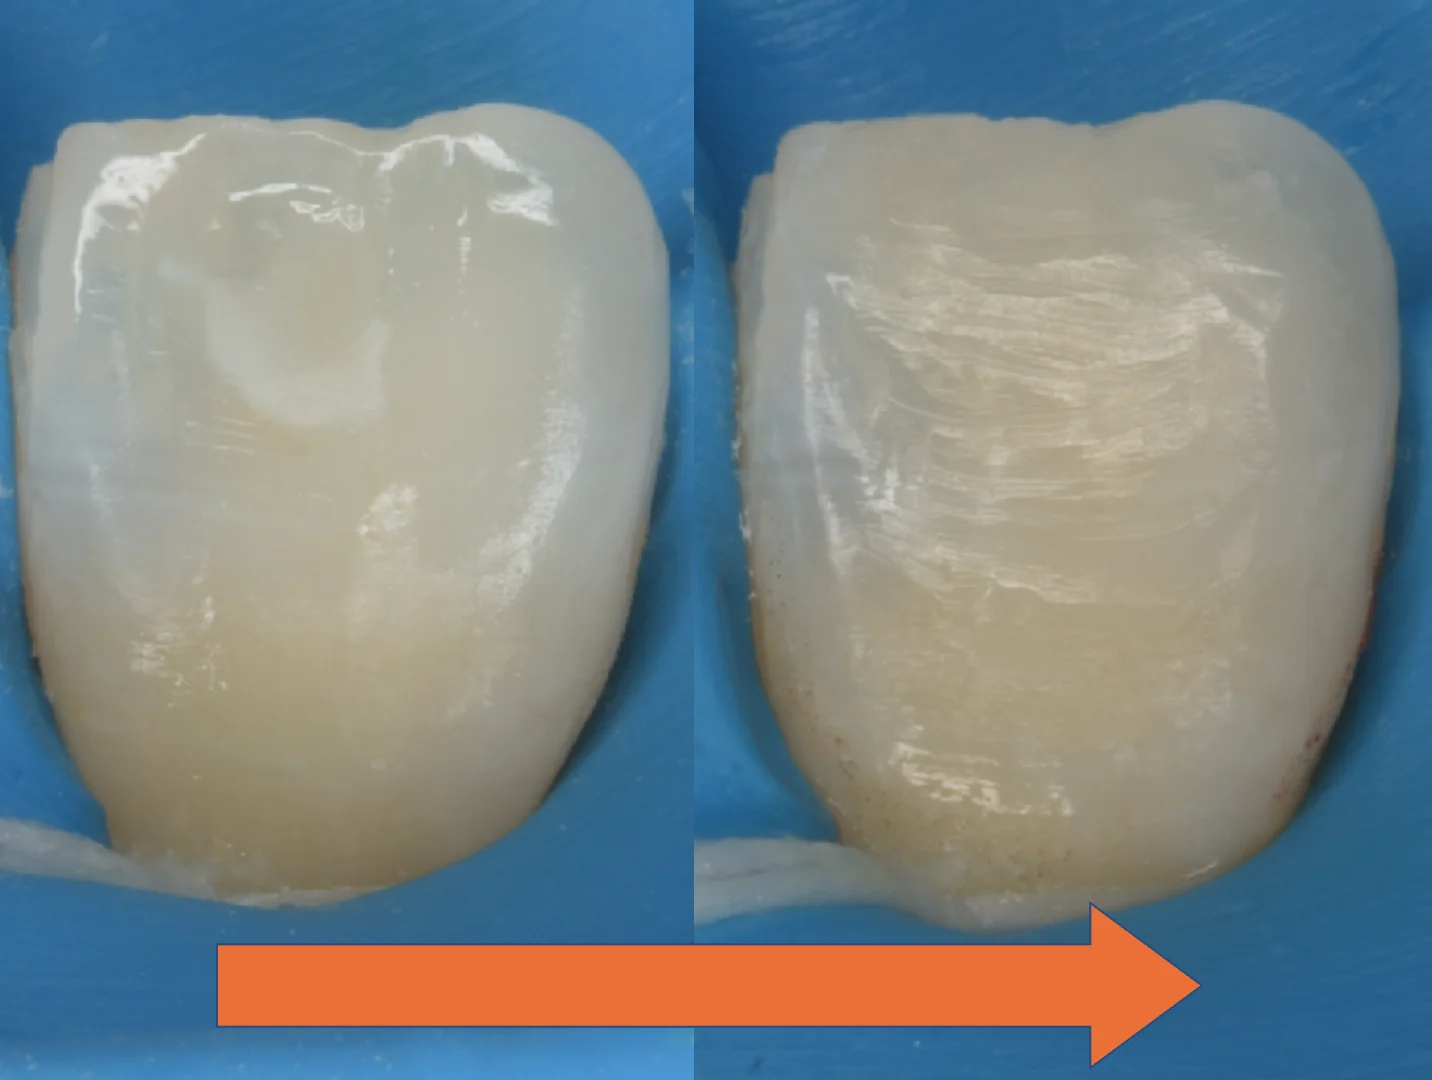

さて。ではこのあとどのようにリカバリーをしたのかというと・・・

こんな感じで残存した部分だけ削って詰めた感じです。

他の歯がそうでしたので、歯ブラシなどでの削れた表面性状をやや強めに表現しています。

ICON治療の際に使用する強い薬剤から歯肉を守るためにつけていたゴムのマスクを外して術前術後で反転して見やすくしたのがこちらになります。

随分と目立たなく、違和感がなくなったのが分かるかと思います。